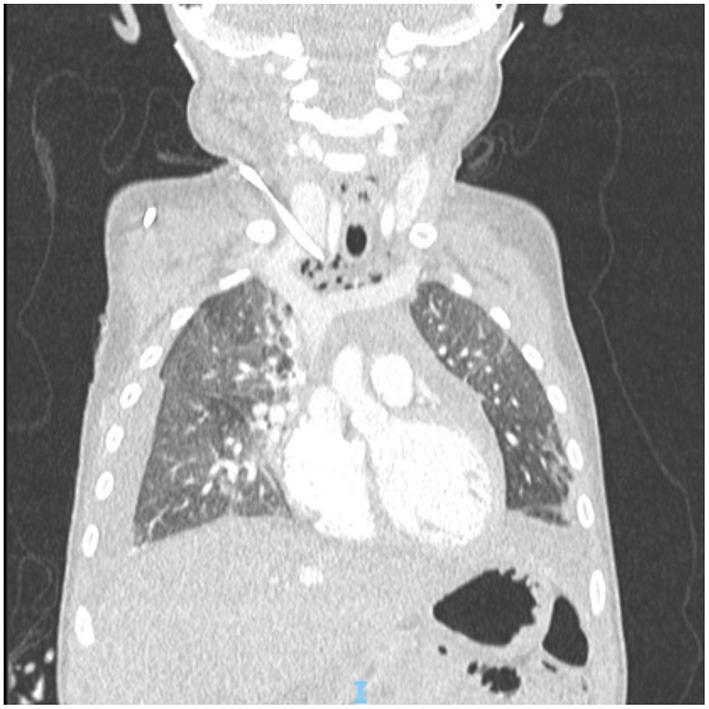

The insertion of long-term central venous catheters is a standard of care for children affected by malignancies, although it can be associated with life-threatening complications. The present paper reports an unusual mechanical complication related to the use of a long term tunneled central venous catheter in a pediatric oncologic patient. An 18 months old child, diagnosed with stage M high-risk retroperitoneal neuroblastoma, underwent ultrasound-guided placement of a 6 Fr bilumen long-term tunneled central venous catheter in the right internal jugular vein prior to the beginning of induction chemotherapy. The correct position of the distal tip of the catheter was confirmed by fluoroscopy. After 4 months of regular use of the device, the patient experienced neck swelling during high-dose chemotherapy infusion. A chest x-ray showed a dislocated catheter and bilateral pleural effusion. CT scan demonstrated the tip of the catheter rupturing the medial wall of the right jugular vein and entering the mediastinum; furthermore, pneumomediastinum, subcutaneous neck emphysema and bilateral pleural effusion were noticed and a thrombus was evident in the right jugular vein at the insertion in the brachiocephalic vein. The patient was then transferred to the Intensive Care Unit and bilateral thoracostomy tubes were placed urgently (500 mL of clear fluid were evacuated from pleural spaces). The dislocated catheter was removed electively on the following day under fluoroscopy. Despite ultrasound-guided placement and long-term uneventful use of the catheter, life-threatening central venous catheter-related mechanical complications can occur; the current case report emphasizes the importance of careful monitoring of patients with central venous catheters in order to quickly diagnose and treat potentially lethal complications.

长期中心静脉导管的插入是治疗恶性肿瘤患儿的一项标准护理措施,尽管它可能会伴有危及生命的并发症。本文报告了一例与儿科肿瘤患者使用长期隧道式中心静脉导管相关的罕见机械并发症。一名18个月大的儿童,被诊断为M期高危腹膜后神经母细胞瘤,在诱导化疗开始前,于右侧颈内静脉接受了超声引导下的6F双腔长期隧道式中心静脉导管置入。通过荧光透视确认了导管远端的正确位置。在该装置正常使用4个月后,患者在高剂量化疗输液期间出现颈部肿胀。胸部X光显示导管移位及双侧胸腔积液。CT扫描显示导管尖端穿破右侧颈静脉内侧壁并进入纵隔;此外,还发现了纵隔气肿、颈部皮下气肿和双侧胸腔积液,且在头臂静脉插入处的右侧颈静脉中有明显血栓。随后患者被转入重症监护病房,并紧急放置了双侧胸腔闭式引流管(从胸腔抽出500毫升清亮液体)。次日在荧光透视下选择性地取出了移位的导管。尽管导管是在超声引导下置入且长期使用无异常情况,但仍可能发生危及生命的与中心静脉导管相关的机械并发症;本病例报告强调了对中心静脉导管患者进行仔细监测以快速诊断和治疗潜在致命并发症的重要性。